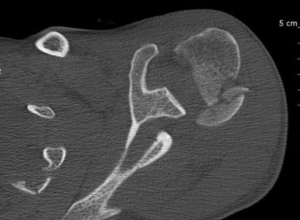

Computed Tomography (CT) Scan

Computed tomography (CT) scans also help the physicians to analyze the bony morphology of the shoulder joint. Before operative management, it is effectively imperative to assess for abnormalities in glenoid version (mean, 4.9 degrees in normal shoulders)[20] according to the Friedman technique,[21] posterior glenoid rim fractures or bone loss, and reverse Malgaigne (Hill-Sachs) lesions. These factors help determining the treatment strategies.